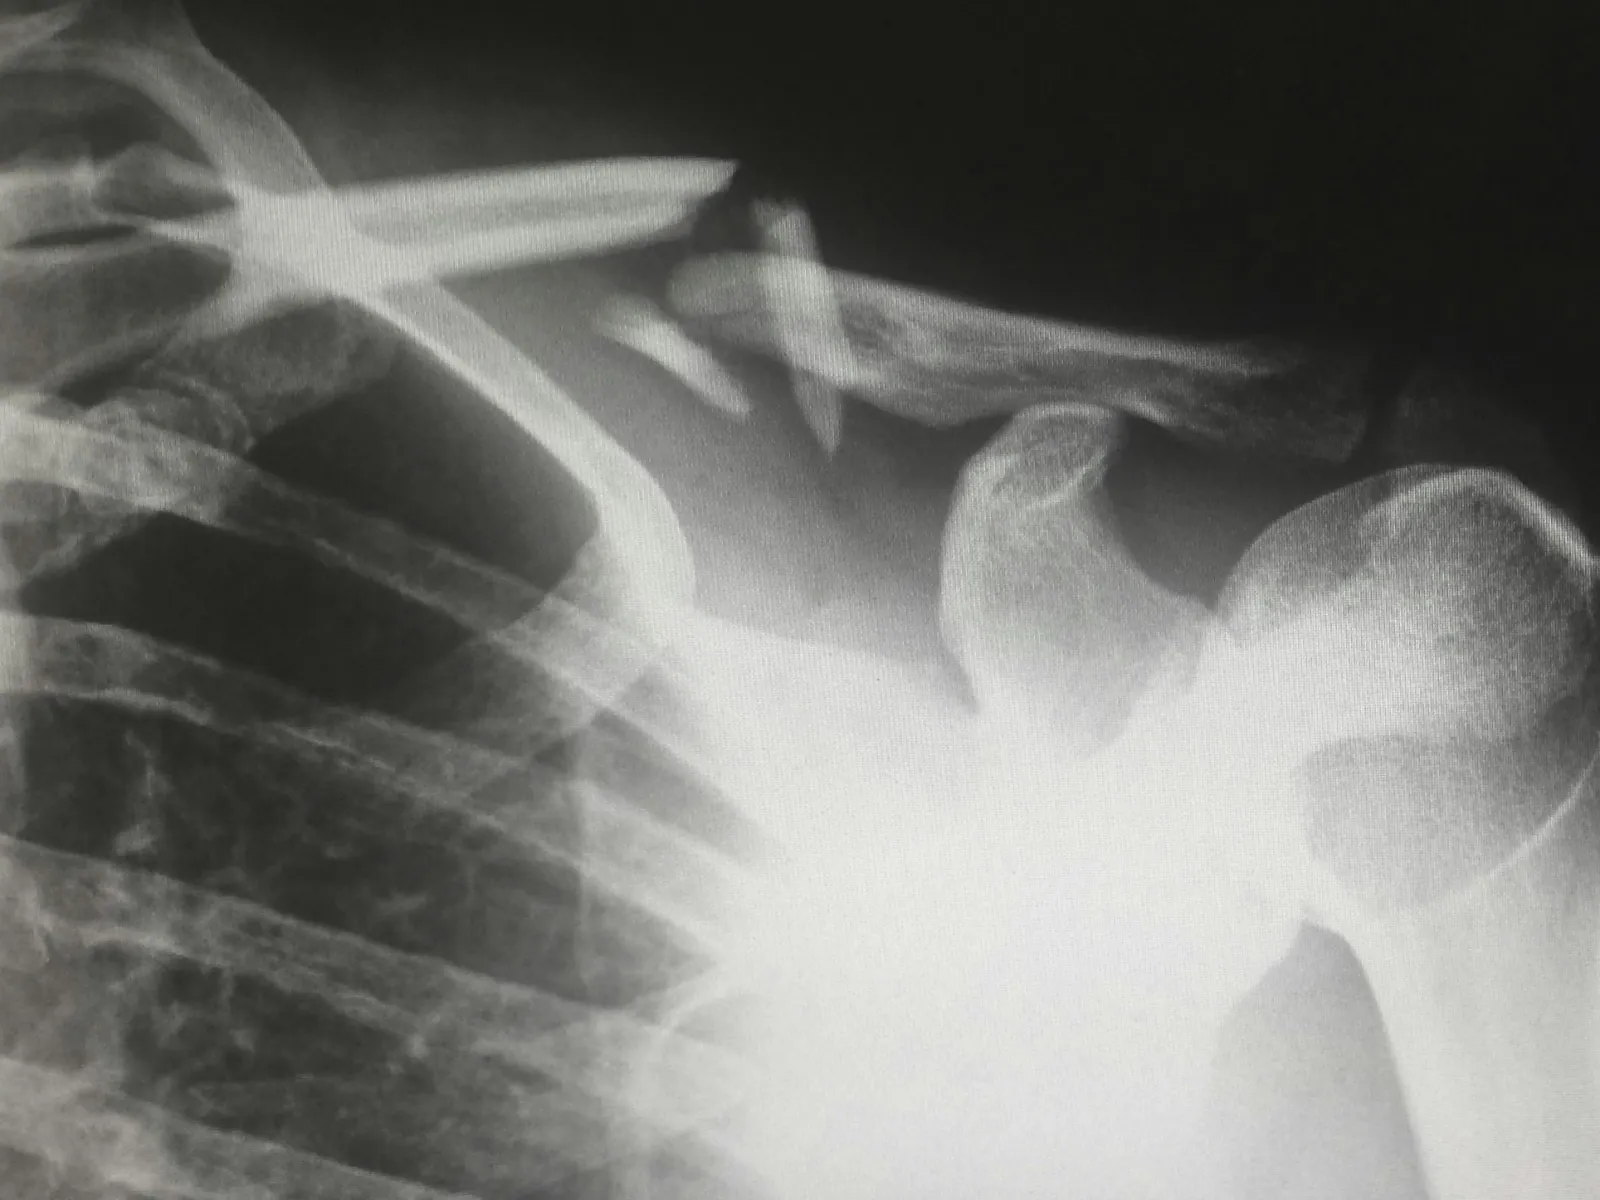

The most obvious clinical example of shoulder instability is a dislocated shoulder. This has gone full circle from a little looseness, to stretching out the soft tissues so much that the humerus ball joint actually jumps (usually going forward) out of the glenoid socket. When shoulder dislocation occurs in a young individual (age 17-40), the is a very high probability that recurrent dislocations will occur in the future. We will talk primarily about adult instability (age 17 and up), although there is a section at the end on Pediatric Glenohumeral Instability.

Shoulder instability is failure of one or more of the stabilizing systems of the shoulder. The static stabilizers can fail throughout a traumatic labral tear of either the anterior (Bankart lesion), posterior or superior (SLAP lesion) portion of the labrum. This is usually associated with a dislocation where the arm is flung violently upward and backward (the windup phase of throwing). This can be seen when a basketball player going up for an overhead shot is stuffed by a blocker. Loss of the anterior or superior bumper allows the humeral ball to slide forward on the flat glenoid bone.

Many times a confirmatory test will be ordered. These include x-rays of the shoulder which is important with a history of traumatic instability. An MRI is a special machine that defines the soft tissue and bony anatomy rather precisely. Sometimes it may be necessary to add a special magnetic dye to the shoulder joint called gadolinium to view a MRI-Anthrogram. This aids in defining tears of the glenoid labrum. The drawback to MRI's is that they are performed with the arms at your side. Not in the provocative position which causes the feeling of instability. As with all special tests, they can assist in the diagnosis, but do not take the place of a well performed physical exam & history.

Other problems may mimic instability and are contained in the list of "other" diagnoses which may be considered, the so-called differential diagnosis list. Luckily for instability, this list is rather short and usually can be distinguished by physical exam or x-ray. Soft tissue interposition, scapular winging due to nerve palsy, seizure disorder, or electrical shock, causing violent muscle contraction with possible dislocation, tumor, and unrecognized fractures are a few causes of instability.